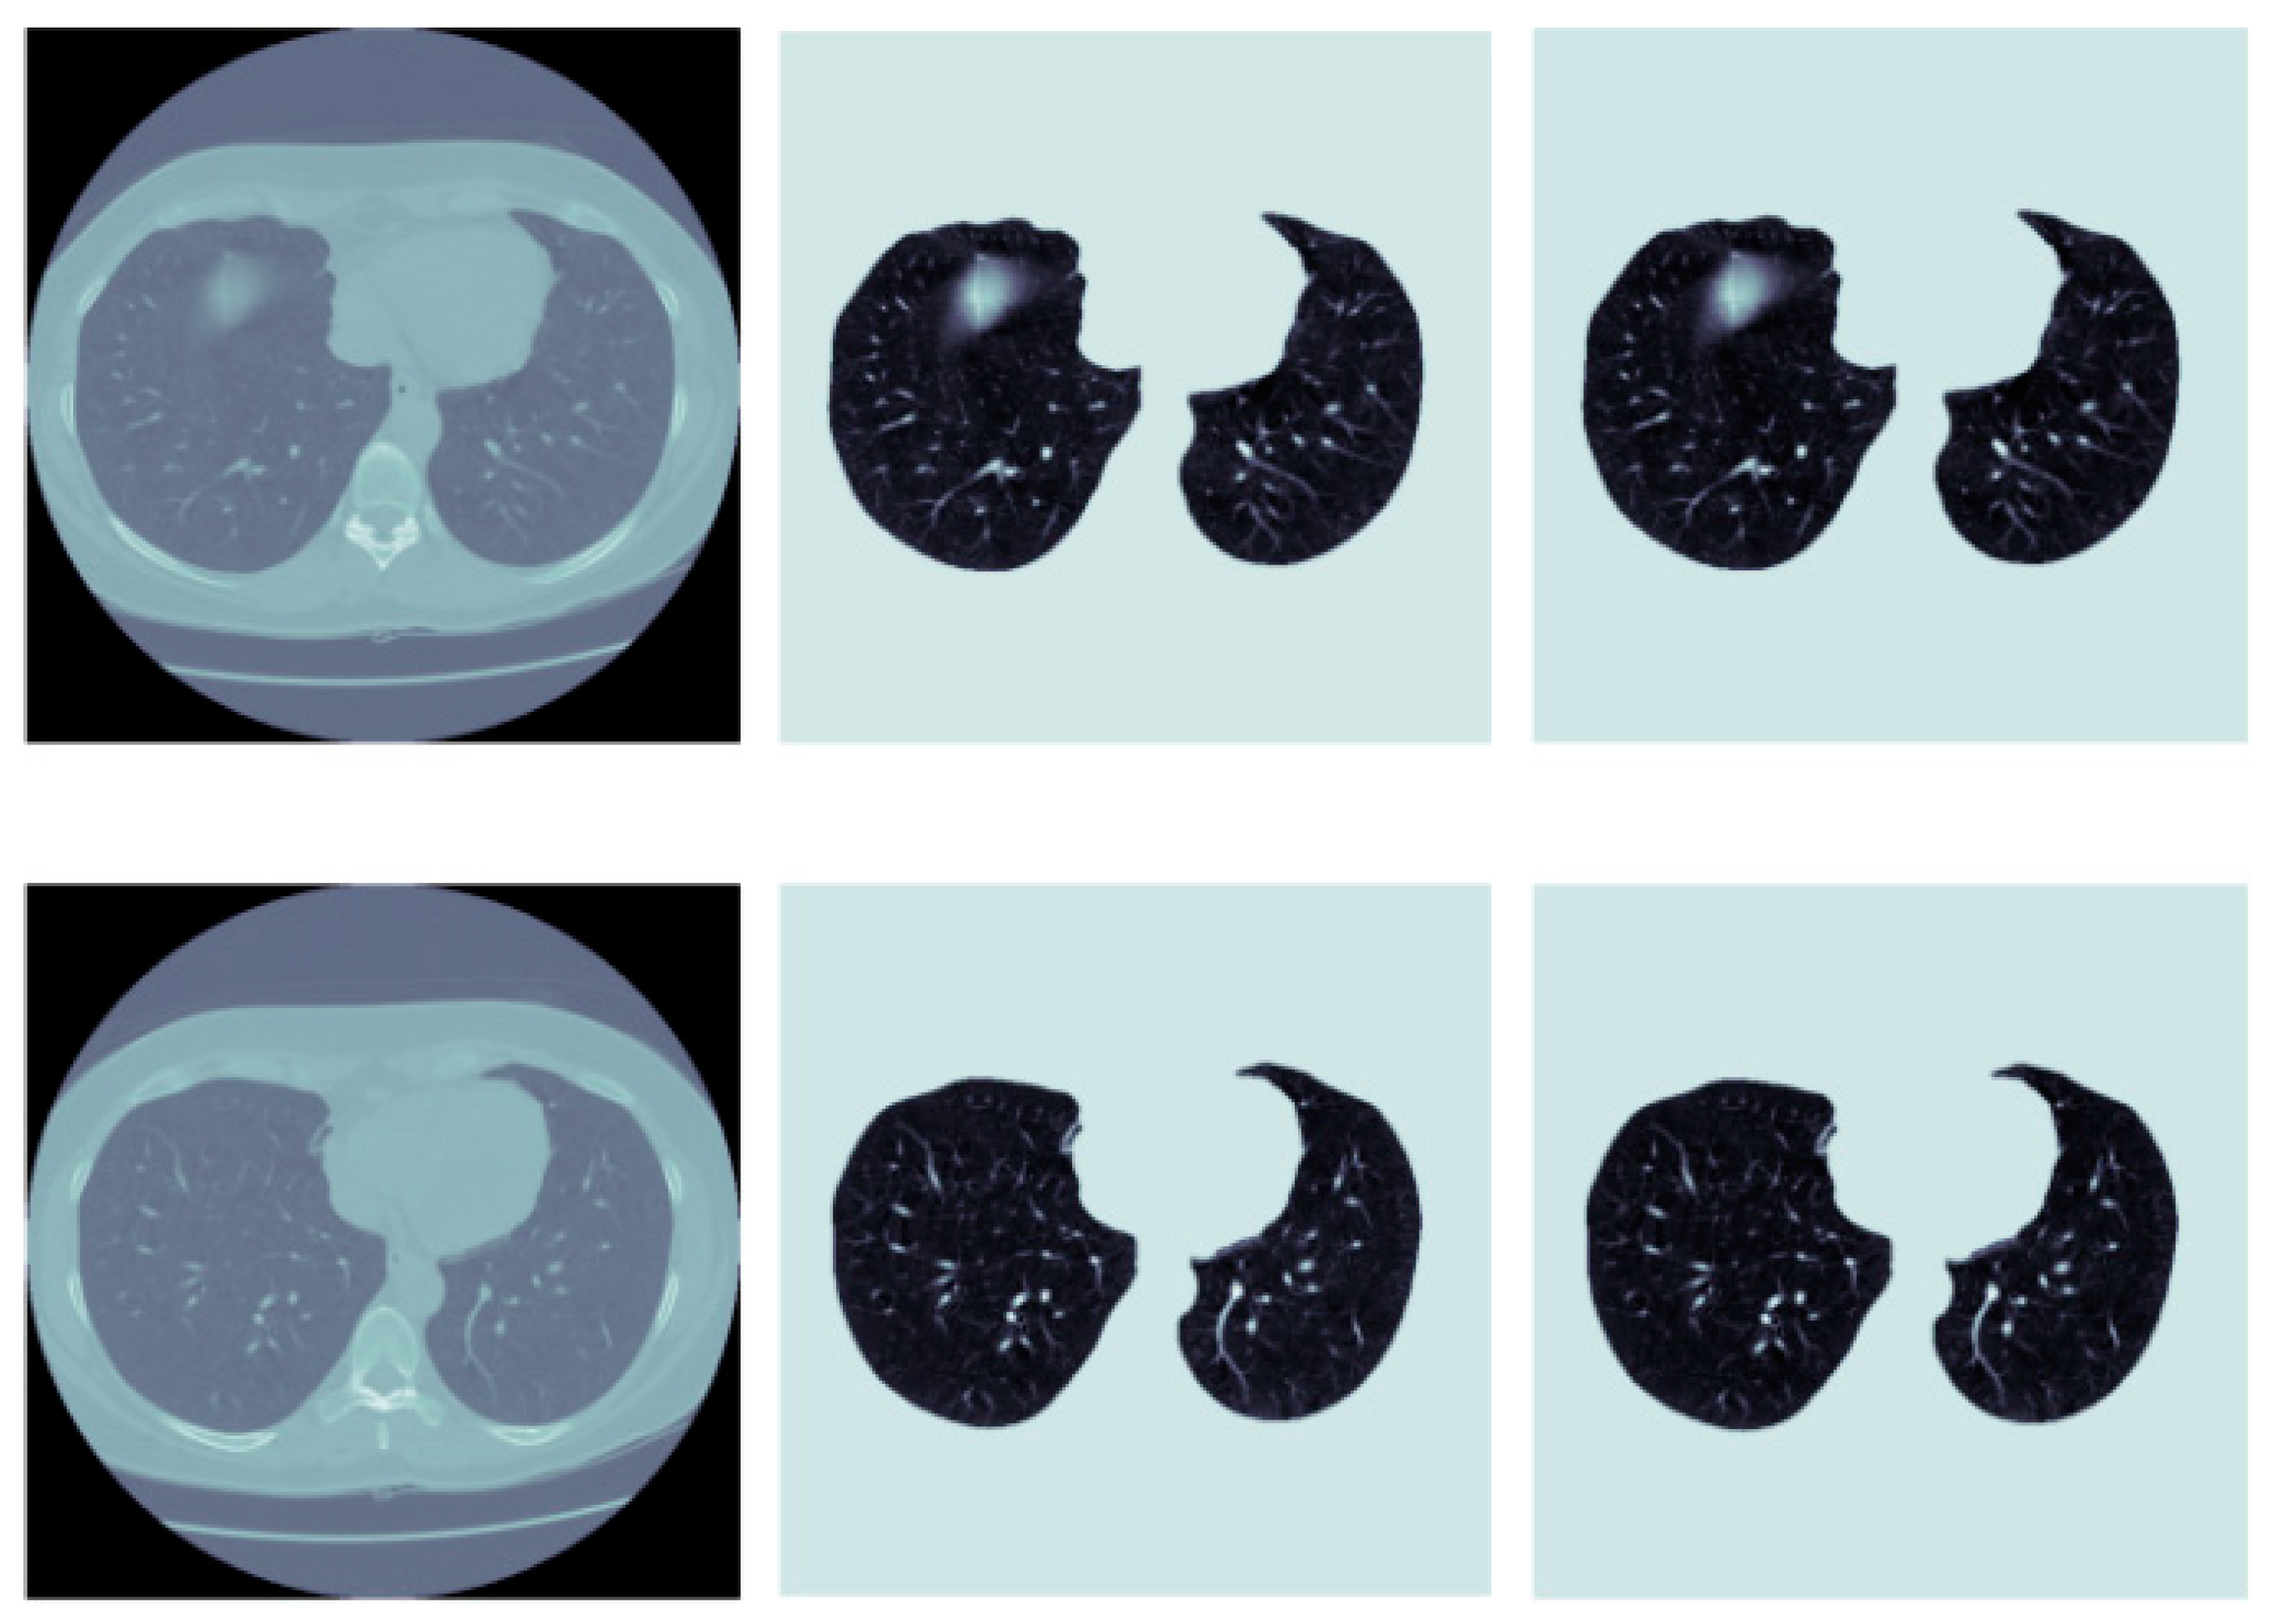

- Park, B.; Park, H.; Lee, S.M.; Seo, J.B.; Kim, N. Lung Segmentation on HRCT and Volumetric CT for Diffuse Interstitial Lung Disease Using Deep Convolutional Neural Networks. J. Digit. Imaging 2019, 32, 1019–1026. [Google Scholar] [CrossRef]